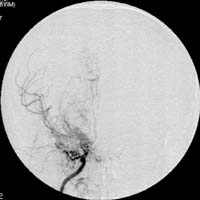

<³úÁ¤µ¿¸Æ±âÇü>

½Ã»óµ¿

ÀÎÁ¢ºÎ ºÎÀ§ÀÇ ³úÁ¤µ¿¸Æ±âÇüÀÇ MRI¿Í Ç÷°üÁ¶¿µ¼ú

¼Ò°ß